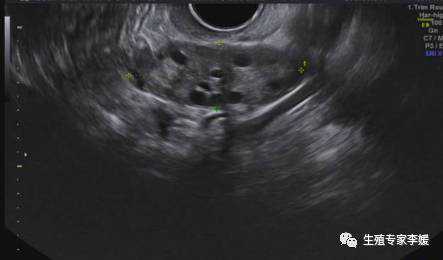

试管卵泡多大可以取卵试管婴儿促排卵时当卵泡在17毫米以上的卵泡有至少3个以上时或者在18毫米以上的卵泡至少有2个以上时可以肌注绒毛膜促性腺激素34-36小时后取卵。长方案取卵促排卵可以适当延迟1-2天。拮抗剂方案不能延迟取卵17毫米的卵泡3个以上就要及时取卵。取卵晚了卵泡可能过于成熟;而取卵早了卵泡大多不成熟可能导致受精不正常,形成的胚胎质量差影响着床从而妊娠率下降。所以试管时卵泡多大可以取卵这是一个非常关键的问题。